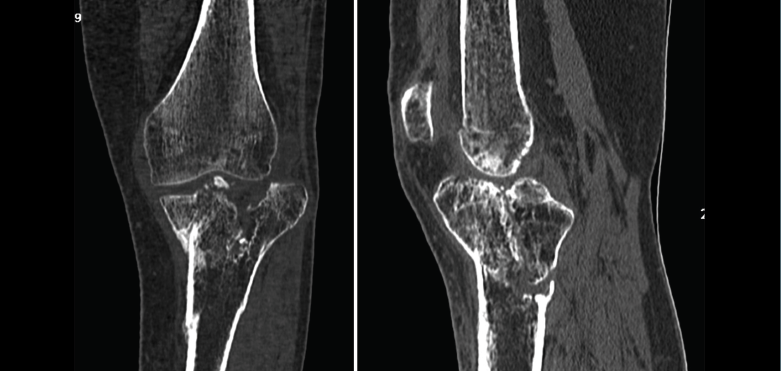

1.2. Tibia (Figura 20)

Figura 20. Corte de reconstrucción coronal de tomografía axial computarizada de rodilla: fractura de ambas mesetas tibiales.